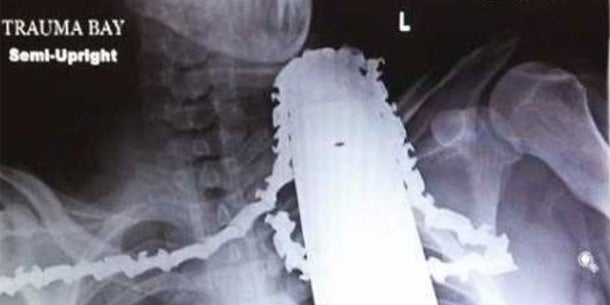

James Valentine (21) aus Pittsburgh war gerade mit einer Kettensäge beim Baumschneiden, als er ausrutschte. Er stürzte so unglücklich, dass sich die Kettensäge fünf Zentimeter tief in seinen Hals bohrte. Ein Mitarbeiter der Rettung berichtet: "Wir haben nur den Motor aus der Kettensäge entfernt, das Sägeblatt ließen wir im Hals stecken. Die Säge nicht zu bewegen, war eine große Herausforderung."

Wie durch ein Wunder wurde keine lebenswichtige Arterie verletzt, konnten die Ärzte im Spital beruhigen. Bei einer kurzen OP wurde die Kettensäge entfernt. Bei einem Interview kurze Zeit später zeigte sich Valentine bereits wieder frohen Mutes: "Du hast, was du hast. Jede Sekunde kann dir etwas passieren, also mach das Beste daraus."